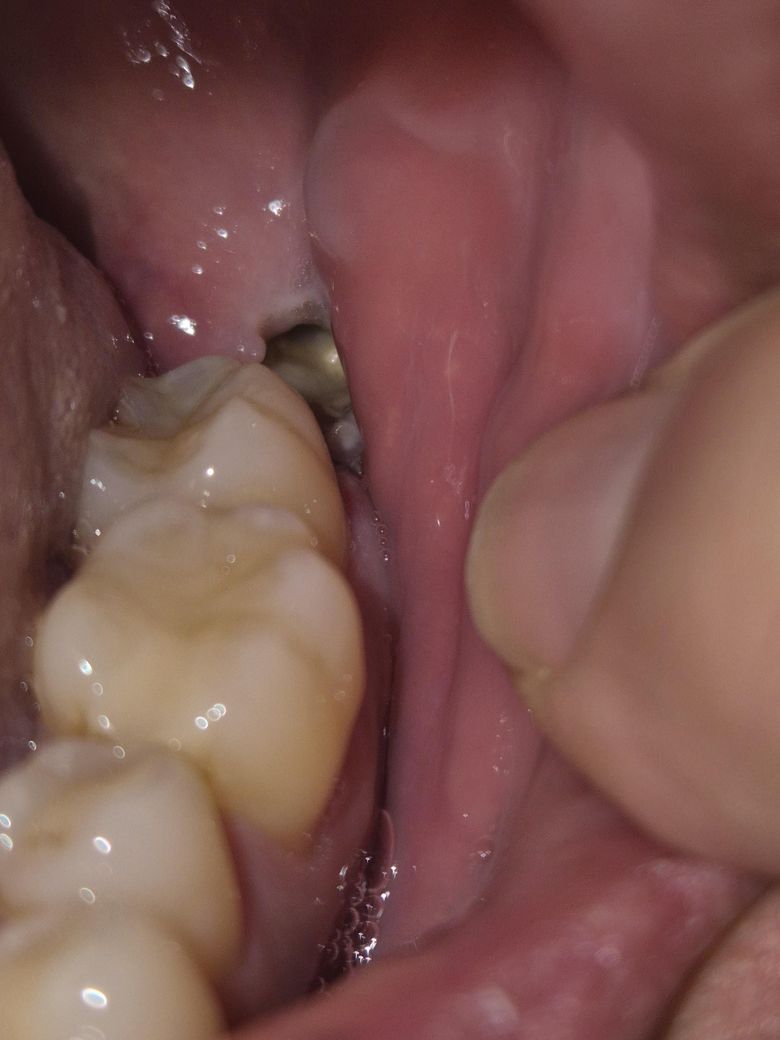

매복사랑니를 5일전에 뽑았는데, 통증이 오늘부터 좀 심한거같습니다.

혹시 드라이소켓이나 다른 부작용일까요

욱씬욱씬 통증이 있고 입을 벌릴때도 아프네요..

사진 다시찍어 첨부드립니다..

현재 사진에서는 크게 문제가 되는 것은 없습니다. 초기에 혈병이 형성되고 시간이 지나면 섬유화 과정을 거쳐 지금과 같은 모습을 보일 수 있습니다. 발치 전에 다량의 치조골 삭제 등이 있었다면 일주일이 지나더라도 약간의 통증은 있을 수 있습니다.

안녕하세요 치과의사 김철진입니다. 사진상으로 보면 드라이소켓일 가능성이 높아 보입니다. 치과에 가셔서 소독을 한번 받아보시는게 좋을것같습니다.

사진으로 봤을 경우에는 혈병이 제대로 생성되지 않아 발치 부위가 노출된 것으로 보입니다 발치된 부위의 혈병이 형성되지 않으면 치유가 늦어지면서 드라이 소켓이 생길 수 있습니다 드라이 소켓은 위반 쪽으로 심한 악취와 극심한 통증을 유발하는 경우가 많습니다 정확한 확인을 위해서 치과에서 진료를 받아 보는 것을 권유 드립니다

증상이나 사진의 양상을 봤을 때 치유부전, 드라이소켓의 가능성이 있어보입니다. 드라이소켓은 흡연, 빨대 사용 등에 의해 잘 유발되고 발치 후 주의사항을 잘 지켰더라도 그러한 부작용이 나타날 가능성은 있긴 합니다. 일단은 증상 개선을 위해 치과 내원해보시기 바랍니다.